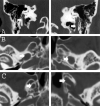

Fig 3.

Thin-section (2.5-mm) axial T1-weighted spoiled gradient-echo gadolinium-enhanced images of the brain obtained at 1.5 T for Gamma knife localization (trigeminal neuralgia). Cranial nerve enlargement (arrows) is most pronounced involving the mastoid or descending segments of cranial nerve VII (A), cisternal segments of cranial nerve III (B), V3 (C), and V2 (D) segments. Faint enhancement is identified.